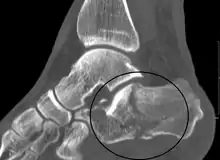

Conventional radiography is usually the initial assessment tool when a calcaneal fracture is suspected. Recommended x-ray views are (a) axial, (b) anteroposterior, (c) oblique and (d) views with dorsiflexion and internal rotation of the foot. However, conventional radiography is limited for visualization of calcaneal anatomy, especially at the subtalar joint. A CT scan is currently the imaging study of choice for evaluating calcaneal injury and has substituted conventional radiography in the classification of calcaneal fractures.[12] Axial and coronal views are obtained for proper visualization of the calcaneus, subtalar, calcaneocuboid and talonavicular joints.

The Angle of Gissane, or "Critical Angle", is the angle formed by the downward and upward slopes of the calcaneal superior surface. On a lateral radiograph, an angle of Gissane > 130° suggests fracture of the posterior subtalar joint surface. Bohler's angle, or the "Tuber Angle", is another normal anatomic landmark seen in lateral radiographs. It is formed by the intersection of 1) a line from the highest point of the posterior articular facet to the highest point of the posterior tuberosity, and 2) a line from the former to the highest point on the anterior articular facet. Bohler's angle is normally 25° to 40°.[13] A decreased angle is indicative of a calcaneal fracture.